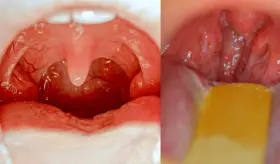

El dolor abdominal que migra desde el ombligo hacia el lado inferior derecho es el síntoma más característico de esta condición que puede derivar en complicaciones graves si no se trata a tiempo.